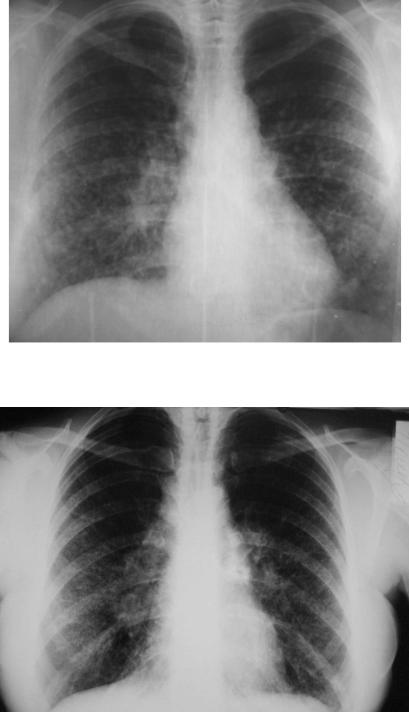

При рентгенологическом исследовании легких на ранних этапах

обнаруживается усиление легочного рисунка за счет интерстициального компонента. Эти изменения чаще ло кализуются на периферии базальных отделов легких. По мере прогрессирования заболе вания интерстициальные изменения становятся все более выраженными, распрост раняясь без четкой границы в апикальном и центральном направлениях. Появление на рентгенограммах небольших участков просветления свидетельствует об образовании кистозных полостей. На заключительных этапах болезни при рентгенологическом исследовании выявляются просветления (кисты) размером до 1 см в диаметре - переход в ячеистое легкое. Изменения в паренхиме легких сопровождаются значительным ограничением подвижности куполов диафрагмы и высоким их стоянием, что некоторыми авторами считается одним из характерных (но не патогномоничных) рент - генологических признаков ИЛФ (рис. 6-2, 6-3).

Локализация поражений может быть самой различной: в нижних легочных полях, в средних, иногда в верхних участках легких. У большинства больных поражение легких симметричное.

Рис. 6-2. Типичная рентгенографическая картина ИЛФ. Двусторонние изменения в нижних отделах легких.

Рис. 6-3. Типичная рентгенологическая картина ИФЛ: двустороннее поражение, признаки легочной гипертензии.